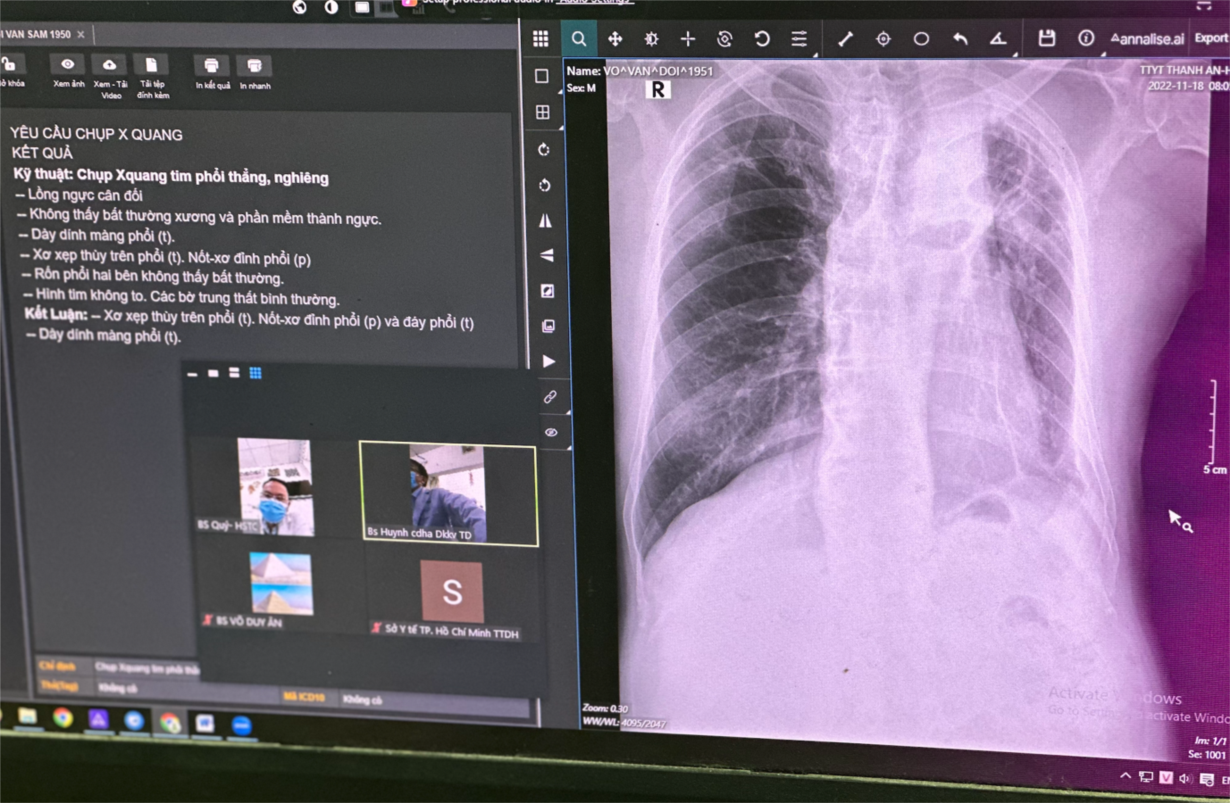

Ngày 18/11/2022, ngay sau khi hướng dẫn cho người bệnh V.V.D 71 tuổi đến Trạm y tế xã Thạnh An để khám và kiểm tra sức khoẻ vì ho ra máu đứng vào đúng vị trí của máy để chụp X-quang phổi, BS Phạm Hải Việt Tỷ - một bác sĩ trẻ của BV ĐKKV Thủ Đức tình nguyện tham gia chương trình luân phiên bác sĩ đến công tác có thời hạn tại xã đảo Thạnh An, chỉ vài động tác chạm tay lên màn hình của máy X-quang, bác sĩ Tỷ đã tự tin đọc các thương tổn trên phim X-quang là xẹp phân thuỳ phổi P, dày màng phổi và tràn dịch màng phổi T.

Bác sĩ trẻ sử dụng máy X-quang có tích hợp AI đã trở thành hiện thực tại Trạm y tế xã đảo Thanh An

Nhờ ứng dụng AI được tích hợp trên máy X-quang kỹ thuật số, các thương tổn trên X- quang phổi nhanh chóng được liệt kê trên màn hình, và nhờ máy X-quang đã được kết nối hệ thống PACs, bác sĩ Tỷ dễ dàng chuyển hình ảnh X-quang phổi vừa chụp để xin ý kiến tư vấn của các bác sĩ chẩn đoán hình ảnh và bác sĩ chuyên khoa Hồi sức của BV ĐKKV Thủ Đức. Chỉ chưa tới 15 phút sau khi xin ý kiến chẩn đoán của các bác sĩ chuyên gia, bác sĩ trẻ đã có một chẩn đoán chính xác và kế hoạch điều trị rõ ràng cho người bệnh.